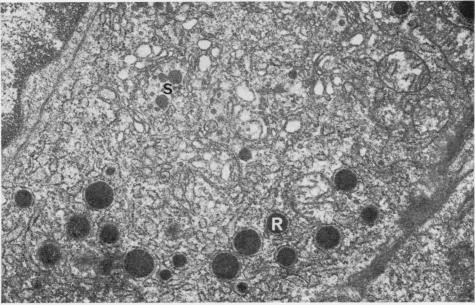

The fine structure is illustrated of plasma cells containing Russell bodies. The material is from chronic inflammatory cell infiltrates in human gastric mucosa and thyroid glands in Graves' disease and Hashimoto's thyroiditis. It is noted that the Russell bodies lie in distended cisternae of rough endoplasmic reticulum and are easily distinguished from less electron-dense ;secretory granules' covered by a smooth membrane that are situated in the Golgi complex.

含拉塞尔小体的浆细胞的精细结构得以呈现。材料取自人类胃黏膜的慢性炎性细胞浸润以及格雷夫斯病和桥本甲状腺炎患者的甲状腺。值得注意的是,拉塞尔小体位于粗面内质网的扩张池内,且易于与位于高尔基体复合体中、被光滑膜覆盖的电子密度较低的“分泌颗粒”区分开来。